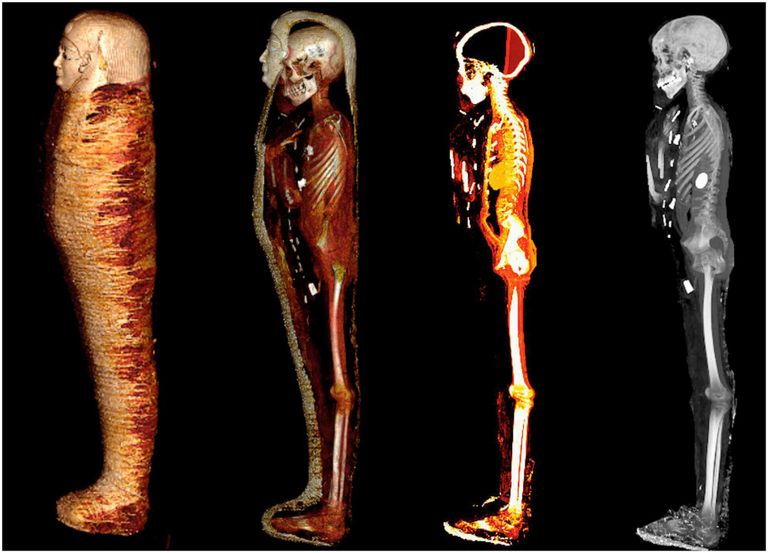

وقالت وزارة السياحة والآثار المصرية، في بيان نشرته عبر صفحتها الرسمية بـ"فيسبوك"، إن التعرف على المومياء جاء بواسطة الأشعة المقطعية والطباعة ثلاثية الأبعاد، وهذا بعد تخزينها لما يزيد على قرن من الزمان داخل بدروم المتحف المصري في ميدان التحرير بالقاهرة.

عملية الفك حدثت بشكل افتراضي باستخدام الأشعة المقطعية، ففي واقع الأمر لم يجر فك اللفائف إطلاقًا، وهو توجه في علم الآثار يشدد على ضرورة عدم لمس المومياوات أو أي شيء مغلق لحمايتها من التدمير.

المومياء لم تتعرض للمس منذ أن تعامل معها وتركها المحنّط، الأشعة المقطعية في هذه الحالة هي طريقة مثلى وفريدة للدراسة، فمن المهم أنها لم تتعرض لأي ضرر خلال البحث.

بدايةً جرت عملية الفحص في حديقة المتحف المصري بجهاز الأشعة المقطعية، وتمكنا من إزالة اللفائف بواسطة برامج عالية الجودة، حتى وجدنا المومياء ترتدي قناعًا مذهبًا، وصدرية مصنوعة من الكارتوناج، وصندل، وبين اللفائف عثرنا على 49 تميمة مرصوصة بشكل متناسق في 3 صفوف.